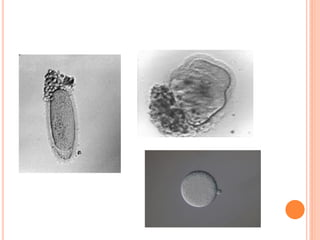

CRITÉRIOS DE AVALIAÇÃO DOS

OÓCITOS

Maturidade

Grau I : uma a três camadas de células

fortemente aderidas

· Grau II : células do cumulus densas e

· Grau III : células expandidas e frouxamente

aderidas

· Grau IV : células muito expandidas e frouxas

· Roto (ZF) : zona pelúcida “fraturada”, com restos

citoplasmáticos

· Atrésico (A) : oócitos pequenos e escuros, ou com

bordas escuras e aspecto irregular

MATURAÇÃO OOCITÁRIA

 Maturação nuclear

 Maturação citoplasmática

 Morfologia

P1                  MI   MII

MORFOLOGIA OOCITÁRIA

ALTERAÇÕES

INTRACITOPLASMÁTICAS

ALTERAÇÕES EXTRACITOPLAMATICAS        CP

EP

ALTERAÇÕES EXTRACITOPLAMATICAS